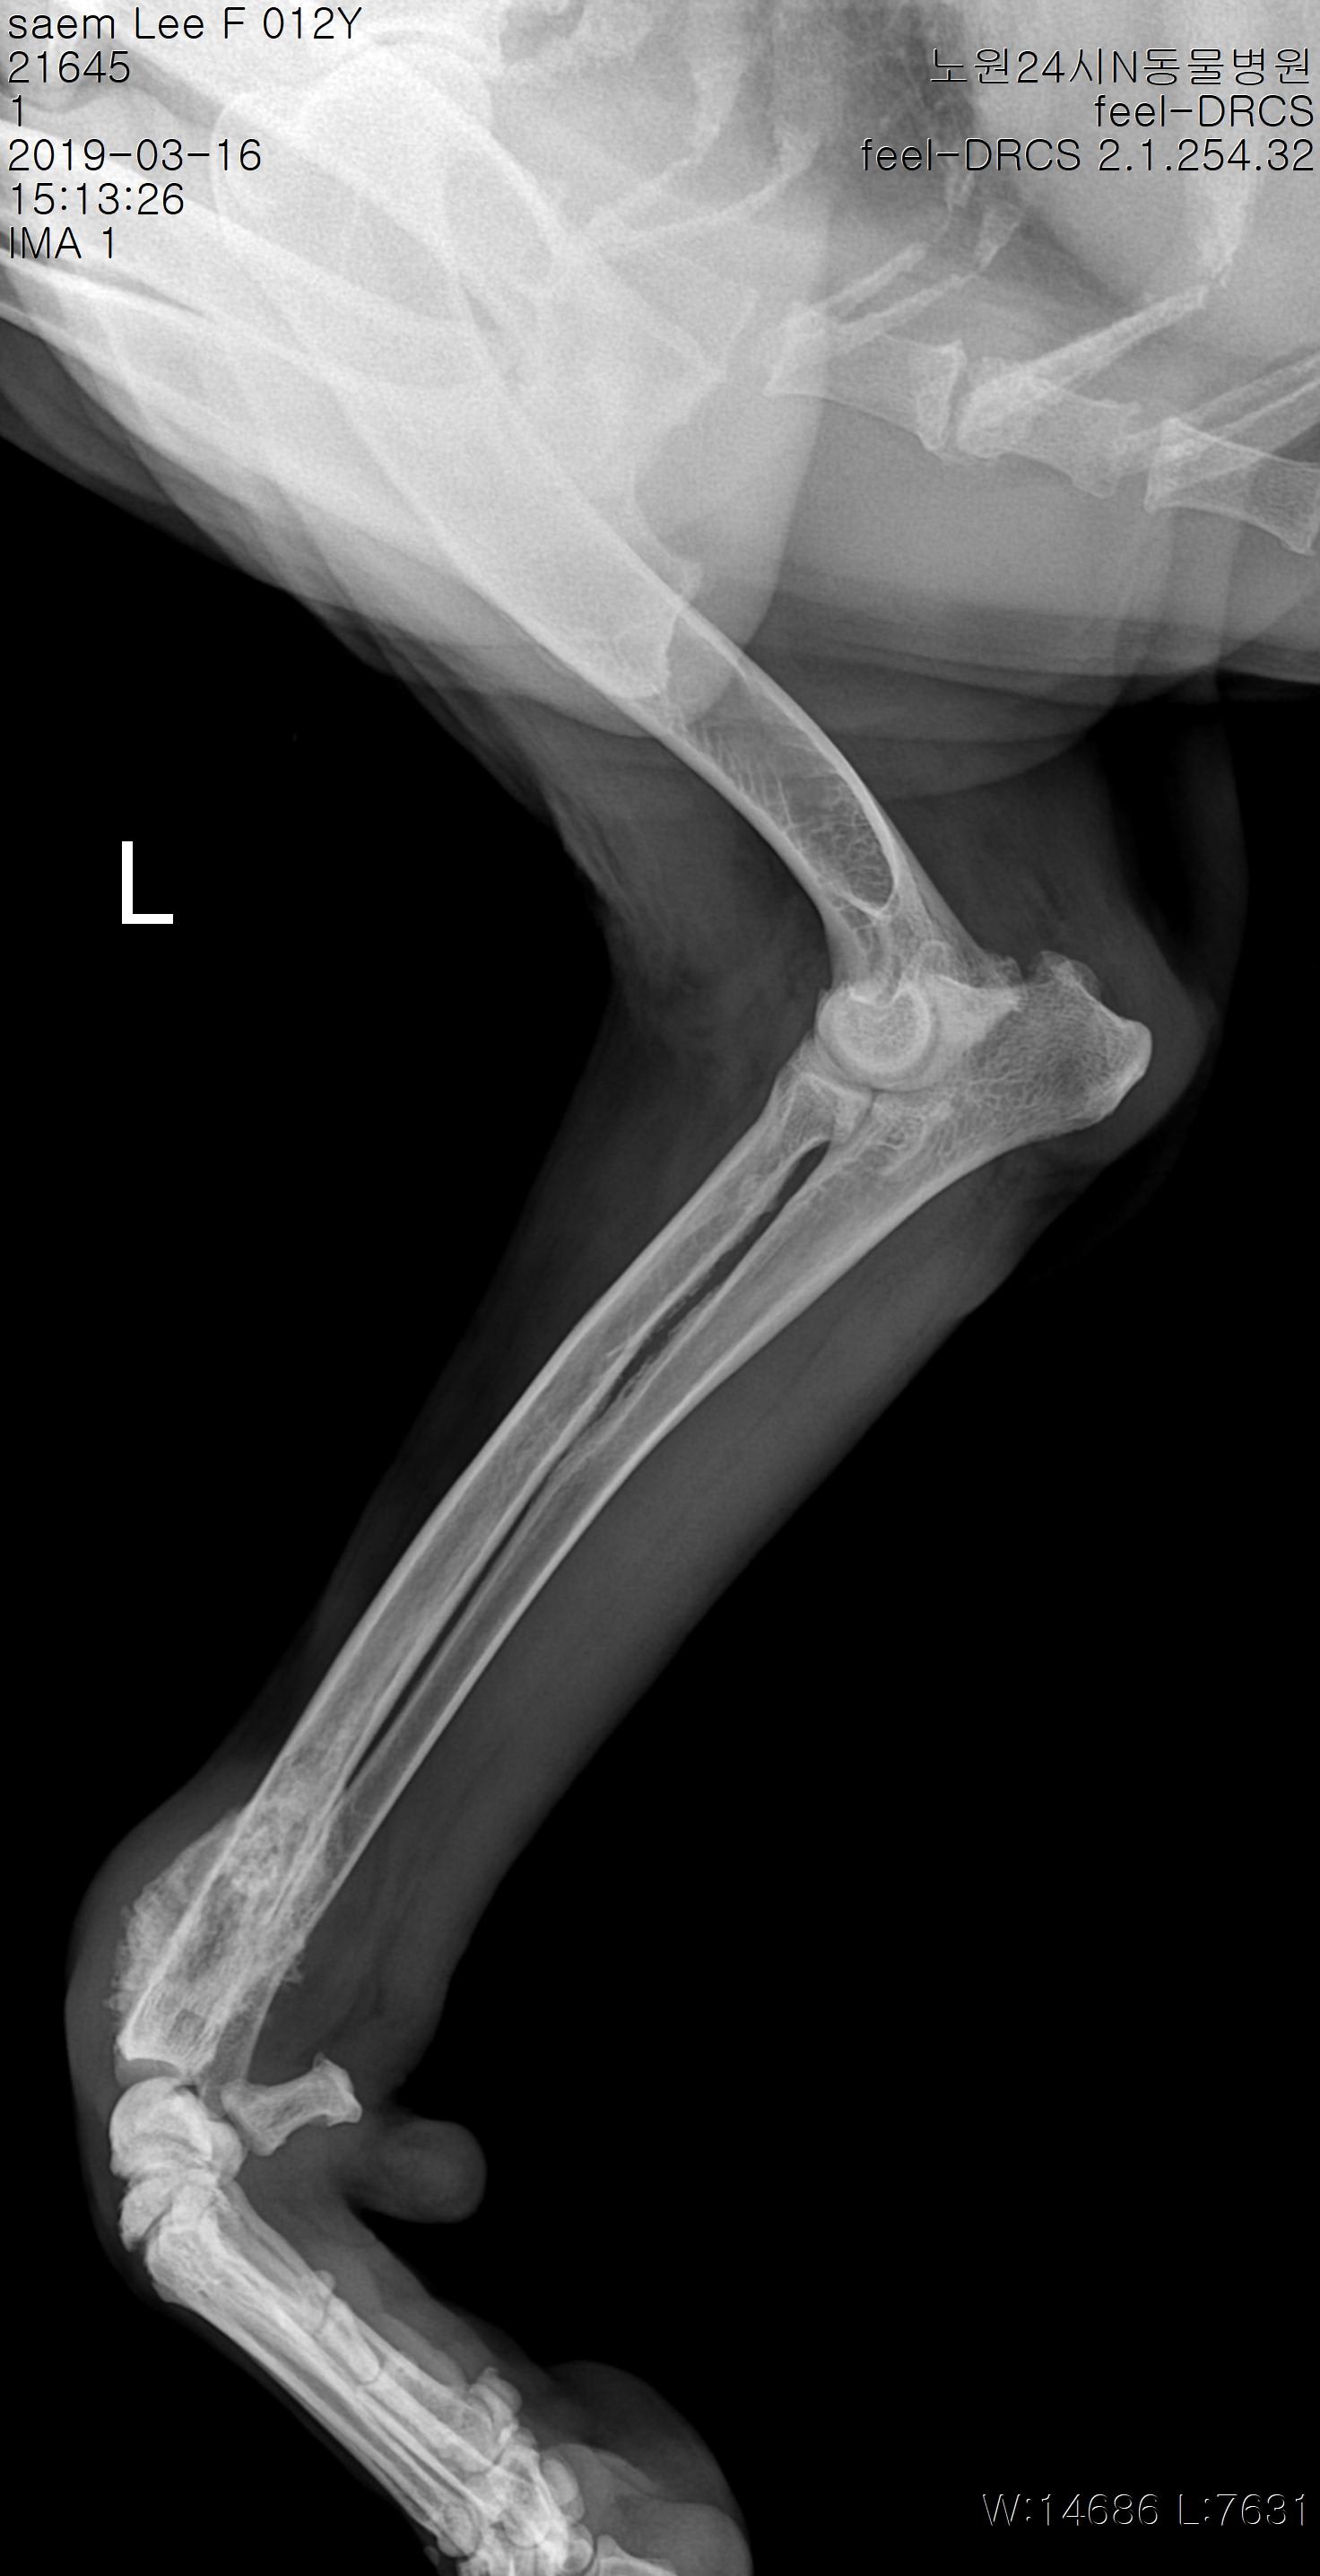

My 12 year dog was diagnosed as bone cancer after x-ray and fine-needle biopsy. I'm devastated since my dog has very poor hip (she received bilateral triple pelvic osteotomy and suffered from severe arthritis in her hips every since. Her hind legs have almost no muscle left) so I don't think I'll let her go through amputation. I'm attaching two images. Would you let me know if there is 0 likelihood of wrong diagnosis?

A bone aspirate is pretty definitive for diagnosing osteosarcoma, and I would trust a pathologist's reading of the images that you posted. I also think the radiograph looks consistent with a primary bone tumor, and the location is typical as well. If you are still interested in some treatment palliative radiation might be an option that could bring some comfort for a period of time without amputation. Ask your vet about palliative options.